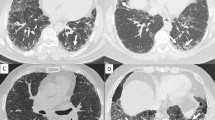

Biopsy proven fibrotic NSIP. MDT diagnosis: idiopathic fibrotic NSIP. Total disease extent at this level: 40 %. Ground glass opacification: 30 %, extent of reticulation 10 %, extent of consolidation 10 %. Traction bronchiectasis score in ground glass opacification: 0. Traction bronchiectasis score in consolidation: 1. Consensed FF score: 0.5

HRCT protocol and image evaluation

A detailed description of the HRCT protocol, HRCT pattern definitions and HRCT scoring method can be found in the online repository. Two thoracic radiologists of 9 and 10 years’ experience scored HRCTs for each patient on the total disease extent, the extent of four interstitial patterns (ground glass opacification, reticulation, honeycombing and consolidation) and emphysema, at six levels. A score of the severity of traction bronchiectasis (0–3) was also assigned. At the end of scoring, each patient had a total disease extent score, for total extent scores for each of the four interstitial patterns, a total emphysema extent score and a total traction bronchiectasis score (examples are shown in Figs. 1, 2 and 3).